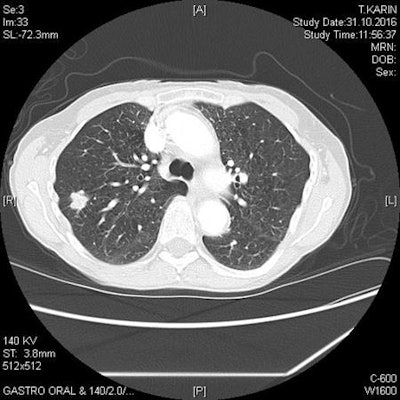

Advances have been made, but until recently, trials that looked at the effectiveness of detecting lung cancer via screening and the ability to save lives have returned disappointing results and no recommendations for use. The sea-change in attitude, however, first began with studies using a low-dose CT scan for the identification of malignant nodules. This led to an unexpectedly high number of cases of lung cancer discovered at early stages, Diederich said.

The randomized National Lung Screening Trial (NLST) was conducted to see if CT could save lives, and the study reported a high number of lung cancer cases discovered at early stages, associated with a 20% reduction in mortality from lung cancer via screening. This was the first time such evidence had been found, and it highlights the significance of early detection, he added.